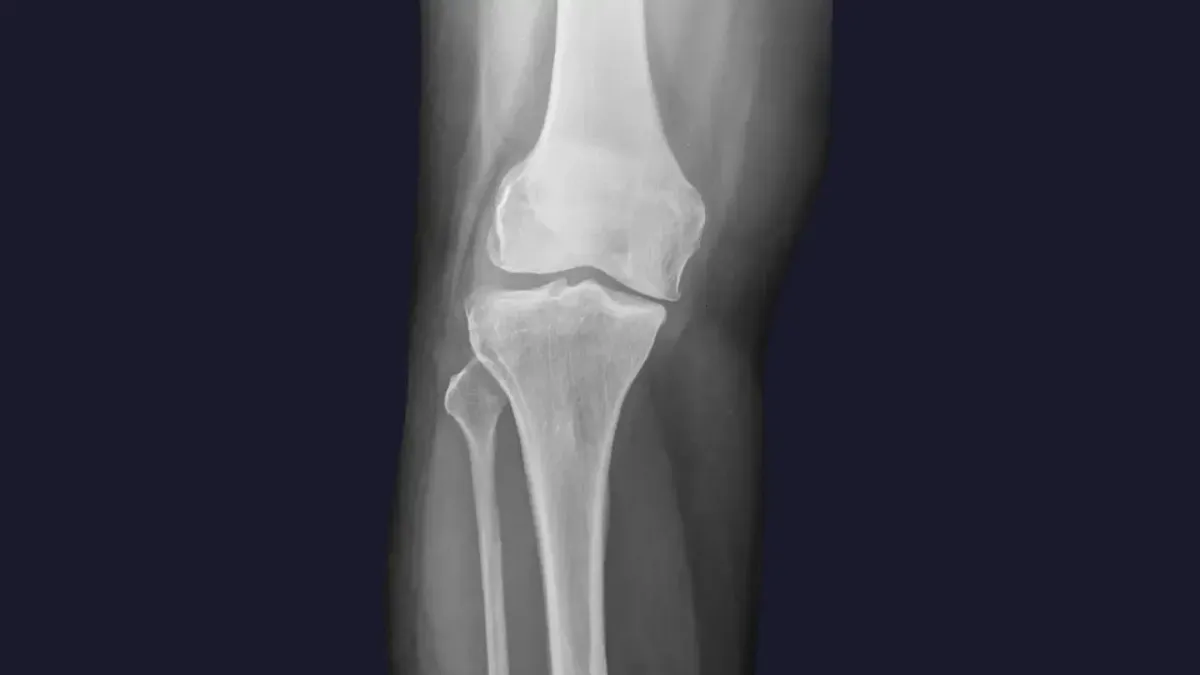

Knee pain is a widespread complaint, often stemming from a variety of sources. Here are some of the common culprits we see in Dayton, OH :

Misalignment: Even subtle misalignments in the knee joint itself, or in the hips and pelvis, can lead to improper tracking of the kneecap, increased wear and tear, and pain.

Arthritis: Degenerative changes in the knee joint can cause stiffness, swelling, and chronic pain.

Ligament or Meniscus Issues: While severe tears may require surgical intervention, chiropractic care can help manage pain and improve function for less severe injuries by optimizing joint mechanics and supporting the healing process.

Poor Biomechanics: Imbalances in the muscles surrounding the knee, or issues with foot mechanics, can place excessive stress on the joint.